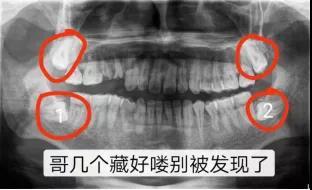

事实上,牙片是牙医的第三双眼睛。一直以为自己就长了三颗智齿呢,直到左侧6号牙坏了,拍了个牙片才知道,原来第四颗智齿长不出来了,但它一直都在。

近中阻生智齿,也就是图中1、2两颗横着向牙列方向长的智齿,非常容易将邻近的牙“顶坏”,所以不得不将这两颗牙拔掉。像智齿这样的下颌槽牙的牙根离面部神经非常近,一不小心就可能伤到神经,导致面部没有知觉。而牙片可以清晰地看到牙根与神经的距离,确定拔牙是不是有风险,这也是为什么拔牙都要拍牙片的原因。这口牙只能用“出车祸”来形容了。本以为下颌大牙先天性缺失,不曾想是牙胚的生长方向错了,大牙长不出来。